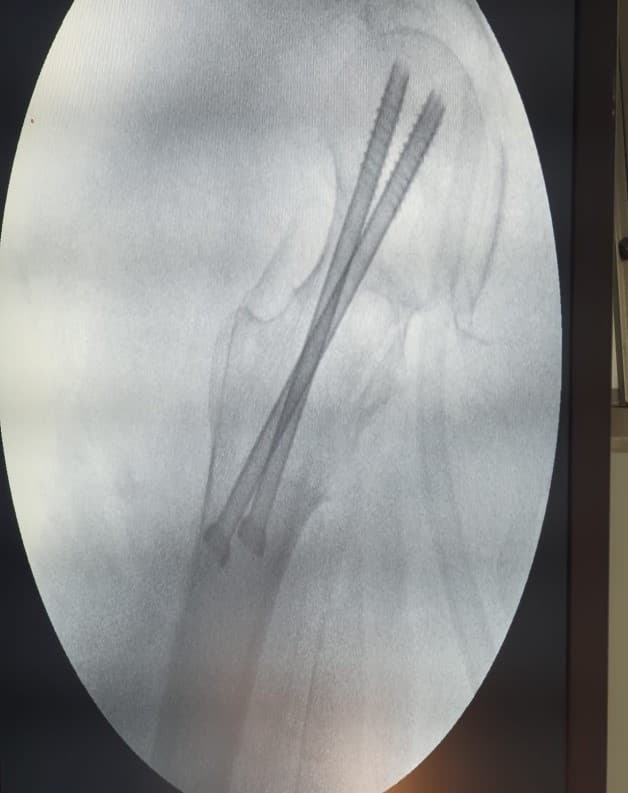

Internal Fixation-хагалгаа, дотор бэхэлгээ / тусгай хадаас

Хугарал засах мэс засал image4

УНТЭ-т хийгдсэн мэс заслын зураг

Hip screw-Түнхний шураг

Хугарал засах мэс засал image6

Хугарал засах мэс засал image7